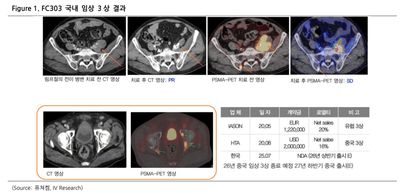

퓨쳐켐(220100)-가시적인 성과들과 미래 기술의 Collaboration